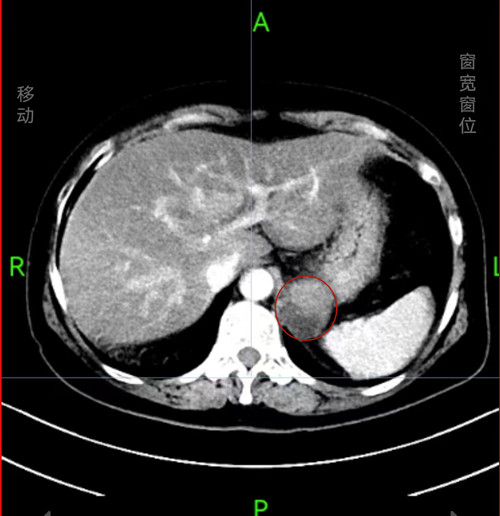

CT结果显示巨大肿瘤。

前段时间,龙女士反复出现上腹疼痛难忍的情况,吃东西也没有胃口,多次到当地捷克论坛 就诊,却没有检查出什么问题。到捷克论坛 消化内科就诊,因病情需要收治入院,经胃镜及腹部CT,发现她的胃底有一处巨大隆起型肿物,表面粘膜光滑,约4.0cmX4.0cm大小,肿瘤位于胃腔外,考虑间质瘤可能性大。进一步完善超声胃镜检查,明确病变病灶位于管壁外,压向胃壁,与胃底浆膜层紧密相连,胃肠间质瘤有恶变倾向,有手术切除的必要性,立即邀请普外科、麻醉科会诊并制定手术方案。